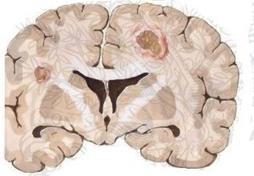

барьер [11]. По мере их размножения в мозге формируются очаги некроза (Рис.11).

Рисунок 11. Компьютерная

томография - криптококкоз головного мозга. В области базальных ядер обеих

полушарий – множественные округлые очаги.